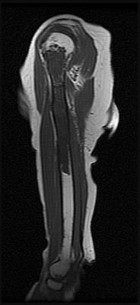

Figures 7a through 7d are the radiograph, MR images, and biopsy specimen of a 35-year-old man who has a painful, slowly enlarging knee mass. Which chromosomal translocation is characteristic of this pathology?

Synovial sarcoma is a soft-tissue sarcoma that usually occurs in young adults. Synovial sarcoma often causes pain, unlike most soft-tissue sarcomas, which generally do not cause pain. Imaging characteristics include soft-tissue calcifications on plain radiographs and a heterogeneous mass that is generally isointense to muscle on T1-weighted images and hyperintense to muscle on T2-weighted images. There are biphasic and monophasic types of synovial sarcoma. The biphasic

type, which is depicted here, has both spindle cell and epithelial components and will stain for both vimentin and cytokeratin. More than 90% of patients with synovial sarcoma have a characteristic genetic translocation of t(X;18), which results in the fusion protein SS18-SSX. This translocation can be stained for use of florescence in situ hybridization technology. t(11;12) is seen in Ewing sarcoma. T(9;22) is seen in extraskeletal myxoid chondrosarcoma. t(12;16) is seen in myxoid liposarcoma.